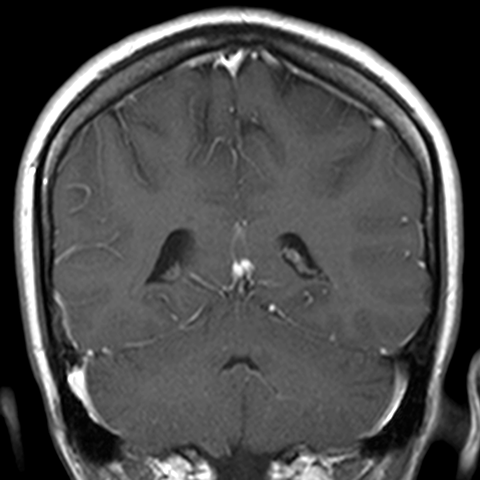

Cranial Meninges (normal) [8 of 8]